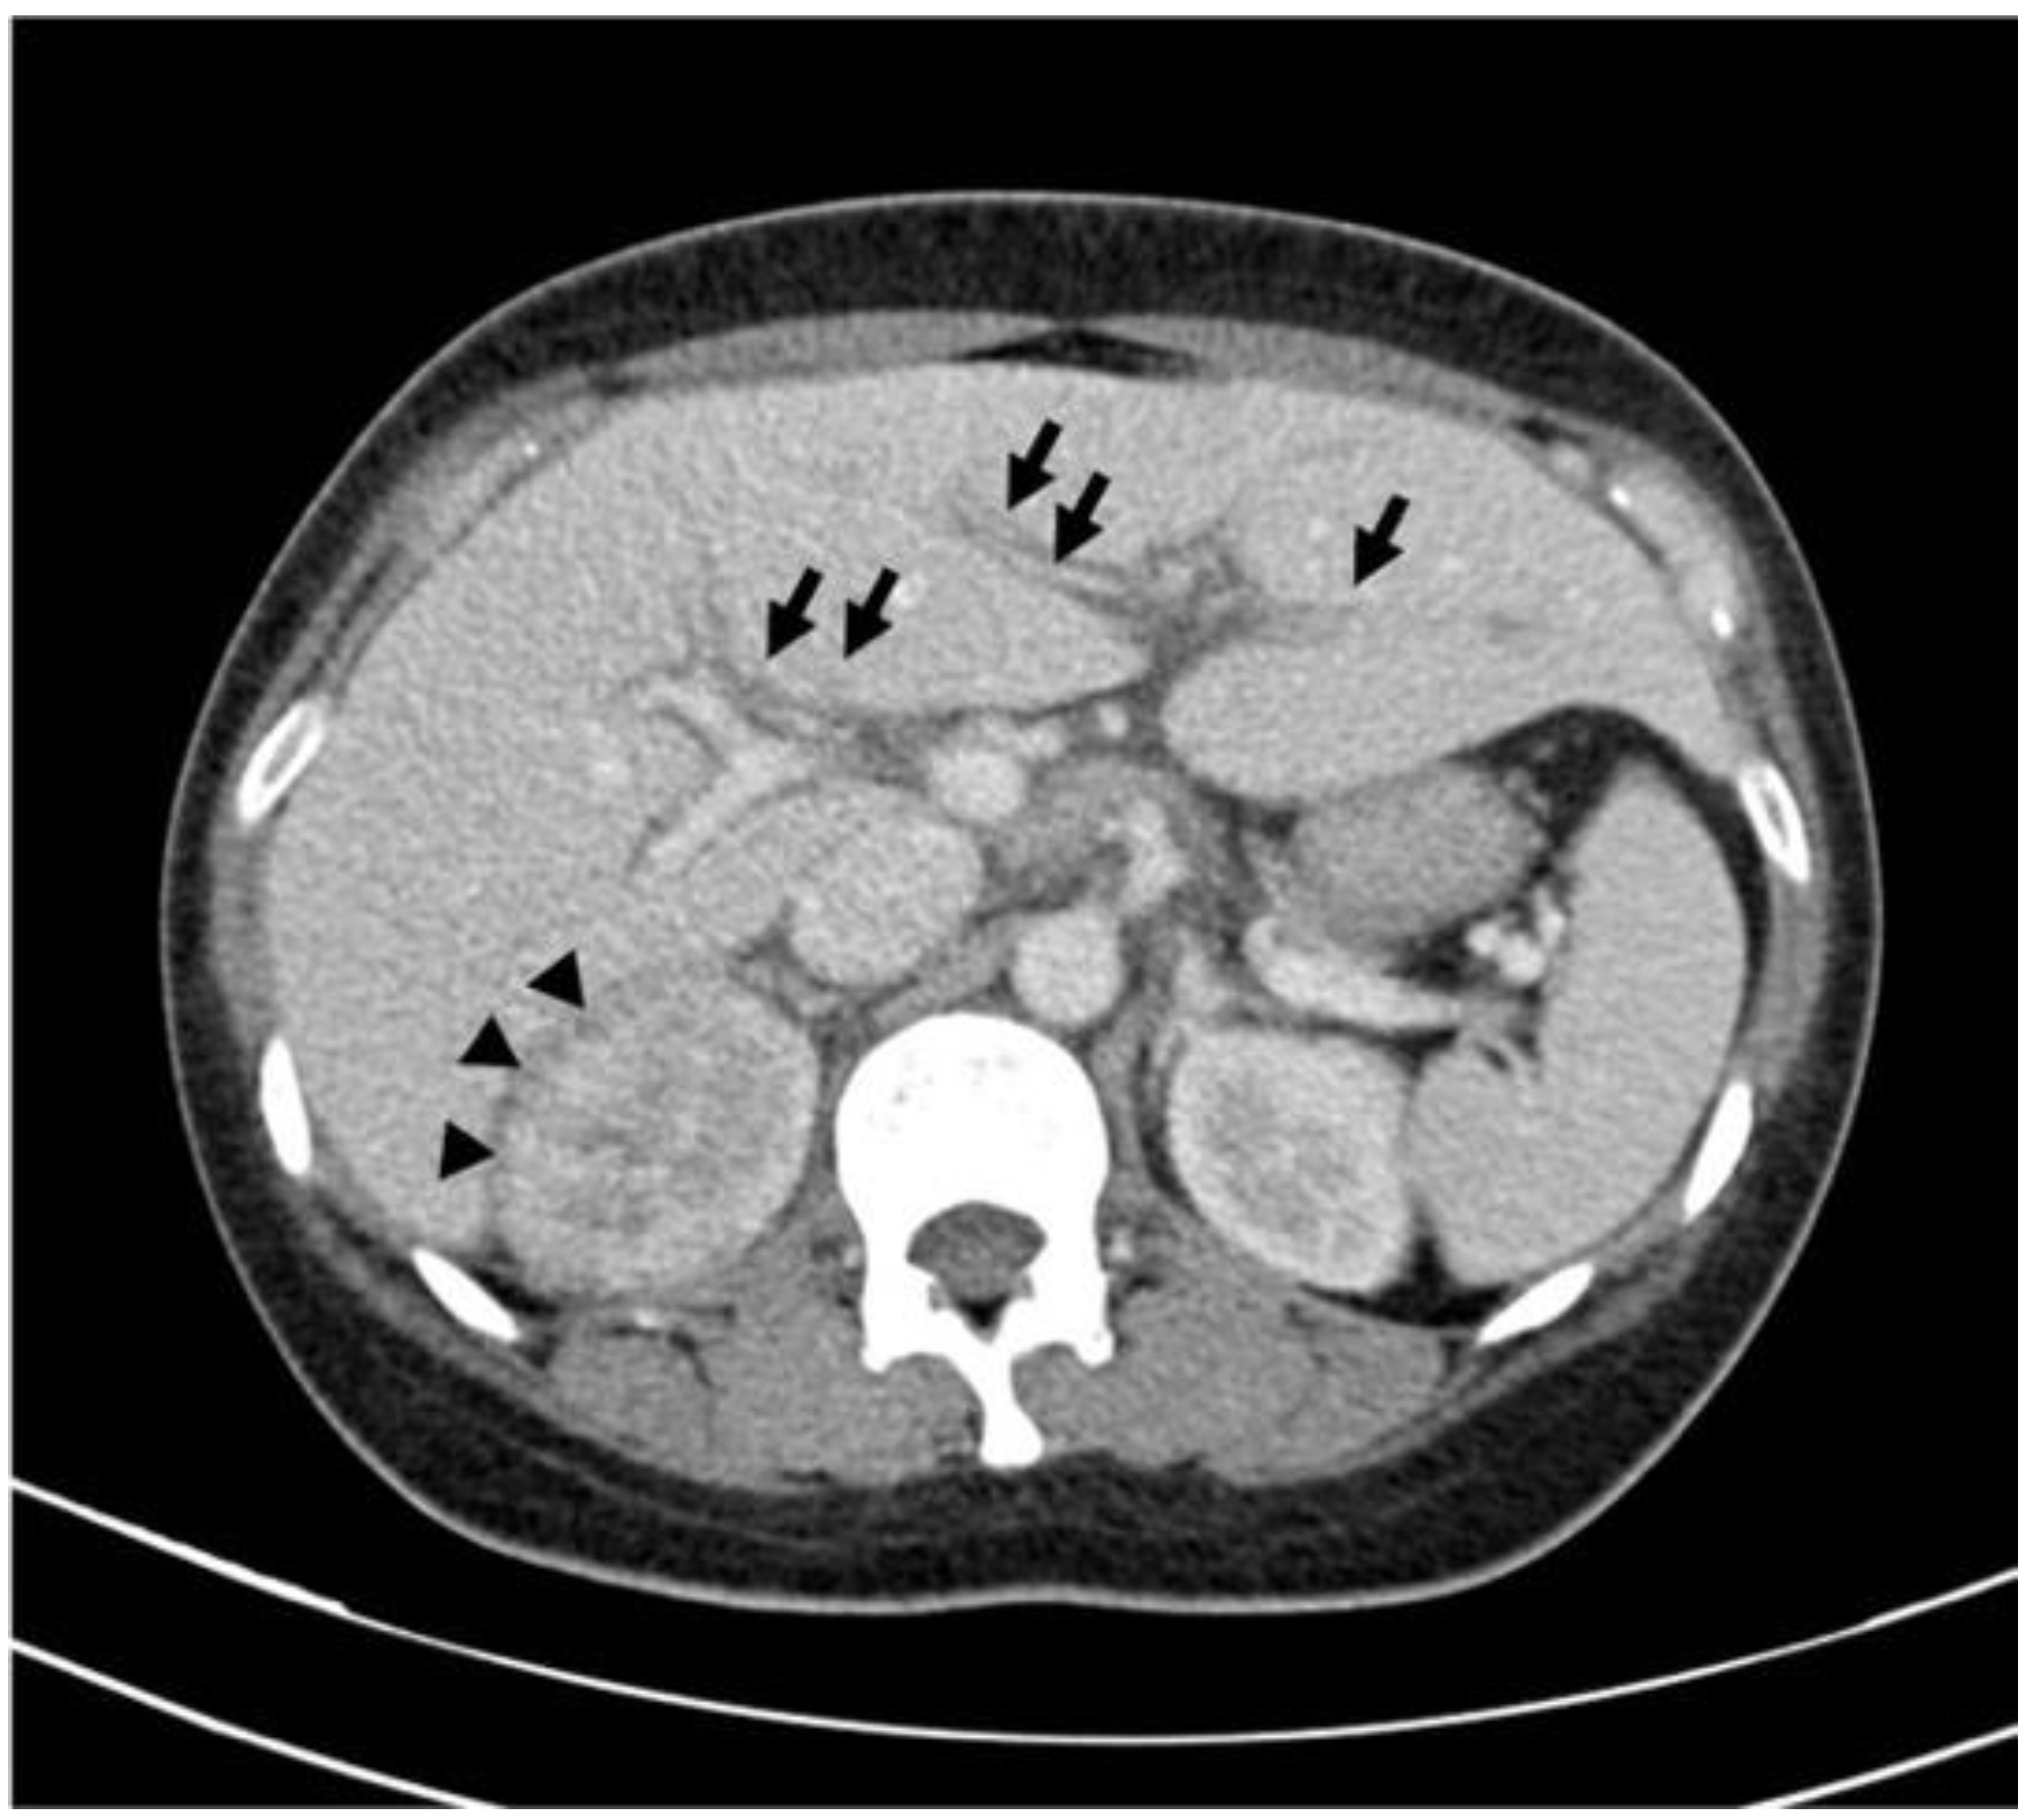

Periportal Edema as an Extrarenal Manifestation of Acute Pyelonephritis